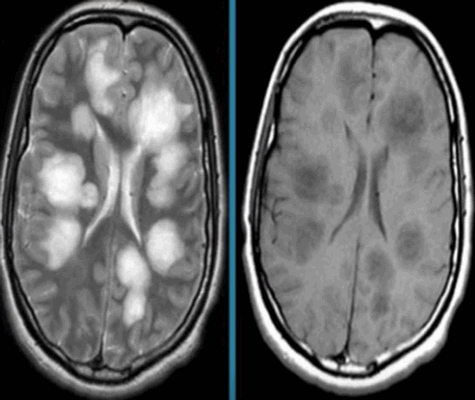

Что покажут снимки МРТ головного мозга при валлеровой дегенерации

- Стадия 1 (острая): До 4 нед. после повреждения на традиционных МР-изображениях не определяются патологические изменения сигнала.

- Стадия 2 (подострая): Спустя 4-14 нед. на Т2-ВИ визуализируется гипоинтенсивная зона, обусловленная начальным, а не биохимическим распадом миелина и компонентов аксона.

- Стадия 3 (хроническая): Гиперинтенсивная зона на Т2-ВИ (распад жиров и липопротеинов, вазогенный отек, глиоз).

- Стадия 4: Атрофия

- Раннее выявление возможно при использовании метода переноса намагниченности (ПМ) и диффузионно-взвешенных изображений.

Валлеровская дегенерация вследствие инсульта в бассейне средней мозговой артерии в левом полушарии большого мозга. Р1_А1К-изображения (а, b) и Т2-ВИ в аксиальной плоскости (с). В зоне, кровоснабжаемой левой средней мозговой артерией, визуализируется кистозный дефект с глиозом (а). Определяется повышенная интенсивность сигнала от пирамидного пути в левой ножке мозга (b) и в продолговатом мозге слева (с).